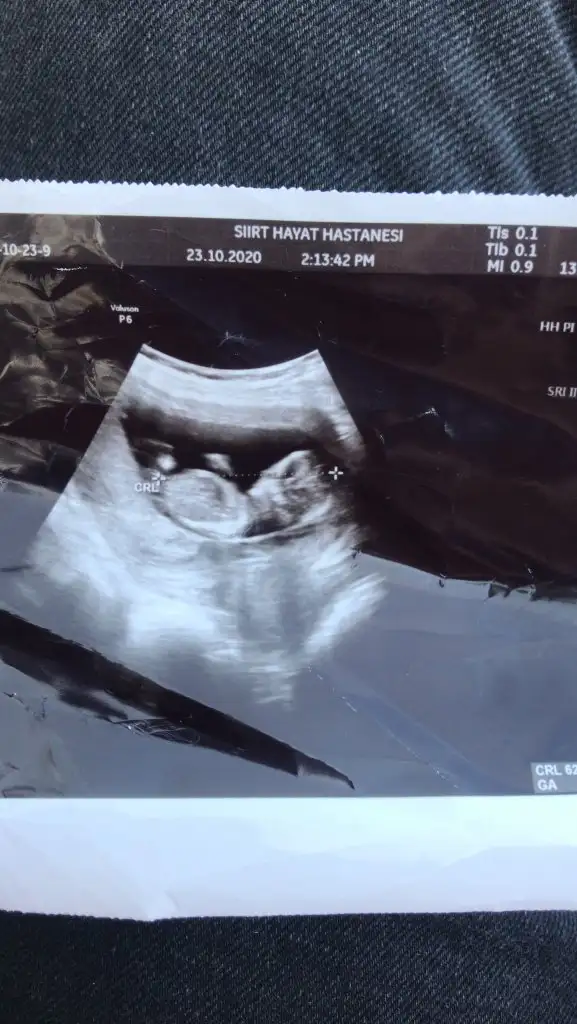

12+3 cinsiyet tahmininden anlayanlar tahminlerinizi alalım :)